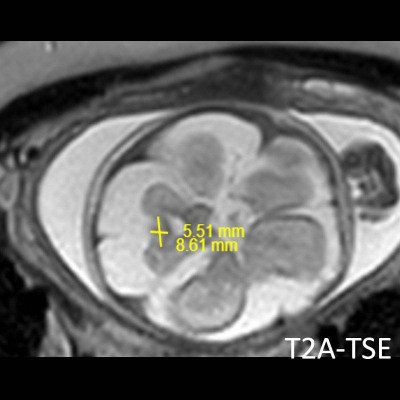

- B) Aksiyel ve sagittal T2A görüntülerde gyrus ve sulkuslarda azalma mevcut olup korteks kalınlaşmış görünümde ve operkulizasyon ayırt edilememiştir. Korteks beyaz cevher ayrımı zor seçilmektedir (ok) Ekstraaksiyel BOS mesafesi artmış görünümdedir (ok). Yapılan ölçümlerde; tegmentovermian açı :8 derece (ok) serebellar vermis boyutları kraniokaudal: 16 mm, aksiyel: 5,5×8,5 mm (ok) ölçülmüş olup BPD:27w ile uyumlu olan fetüste haftasıyla uygun olarak değerlendirilmiştir.